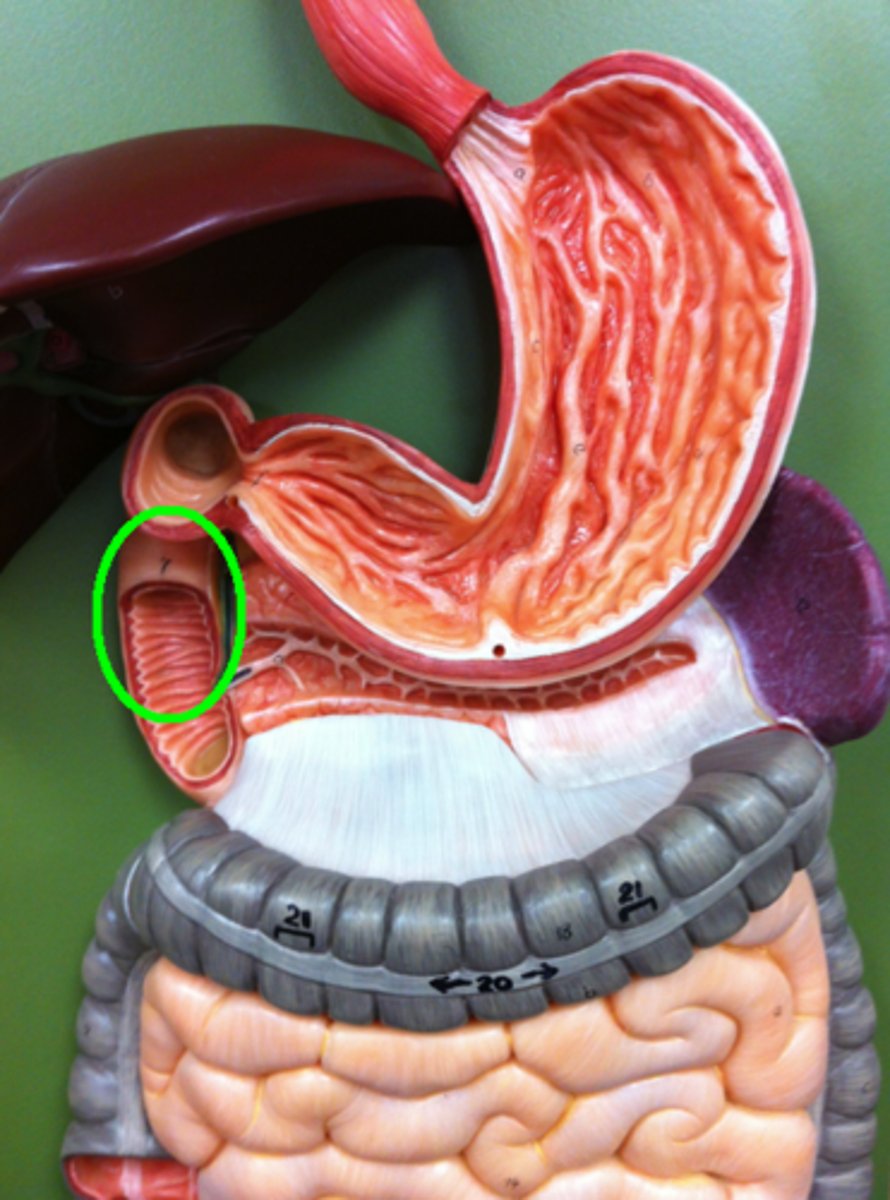

pylorus

pyloric sphincter

rugae

duodenum

plicae circulares / circular folds

what are the folds